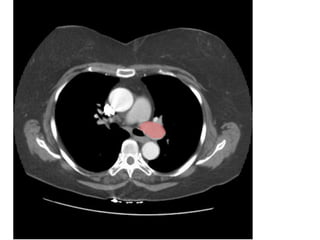

Thất

phải

Thất trái

Figure 9. PE ở bn nữ 42 tuổi, đau ngực và khó thở nhiều.

- Hình ảnh thất phải dãn lớn hơn thất trái.

12